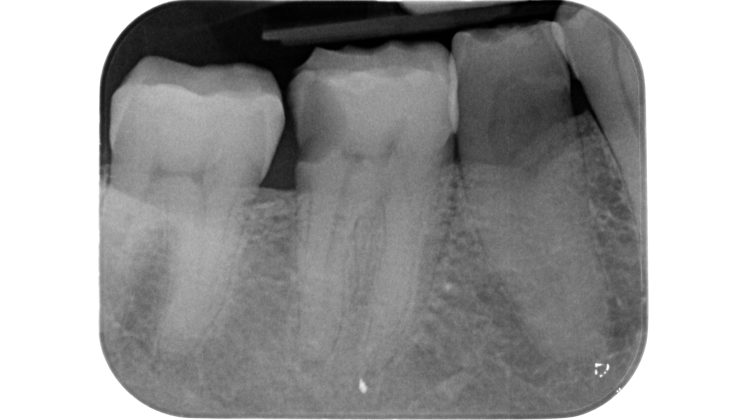

Una cavità d’accesso inadeguata per posizione, profondità ed estensione può determinare serie difficoltà nelle fasi successive, rendendo ad esempio difficile la localizzazione degli orifizi canalari, sottoponendo a eccessivo stress gli strumenti meccanici utilizzati o determinando un indebolimento della struttura dentale residua (Figure 1-5).

L’esecuzione di una corretta cavità d’accesso trae origine innanzitutto da una preliminare valutazione clinica e radiografica dell’elemento da trattare.

Devono essere valutate con molta attenzione la posizione dell’elemento in arcata e la sua inclinazione (Figure 6-7), l’entità e la posizione del processo carioso se presente, gli eventuali restauri posizionati sul dente e i rapporti con il parodonto: tutte queste considerazioni permetteranno al clinico di capire innanzitutto la mantenibilità e la possibilità di isolare mediante diga di gomma il dente. L’interpretazione degli esami radiografici consentirà inoltre di valutare alcuni parametri preoperatori di notevole importanza:

Un’attenta analisi di questi dati clinici e radiografici consentirà al clinico di ridurre notevolmente il rischio di errori grossolani in questa delicata fase del trattamento.

Lo strumentario minimo che un operatore dovrebbe avere a disposizione per eseguire una terapia canalare è rappresentato da un sistema di ingrandimento e una contestuale sorgente luminosa coassiale: questi dispositivi consentono di poter gestire anche situazioni cliniche complesse (es. calcificazioni, importanti discromie, esplorazione di incrinature che si approfondiscono all’interno della camera pulpare). L’utilizzo del microscopio operatorio garantisce un ulteriore passo in avanti tale da aumentare la predicibilità del trattamento, ma ad oggi è ancora uno strumento utilizzato da pochi professionisti ed in particolare da chi si dedica a questa branca in modo specialistico.